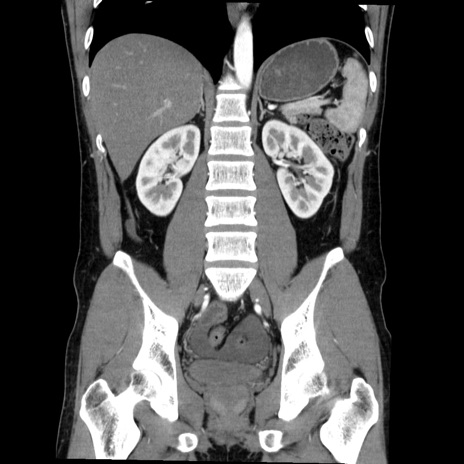

症例36(冠状断像)

【症例】20歳代 男性

【主訴】心窩部痛

【現病歴】今朝より上腹部痛あり。一旦軽快していたが再度出現したため救急要請。昨日夕に白身の魚を含む刺身を食べた。

【身体所見】BP 136/89mmHg、HR 74/min、BT 37.0℃、腹部:膨満、軟、心窩部に圧痛あり。反跳痛なし、筋性防御なし、腸雑音やや亢進あり。

【データ】WBC 17700、CRP 0.48